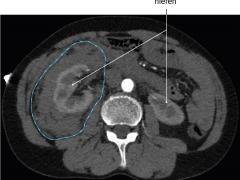

Spontaan retroperitoneaal hematoom